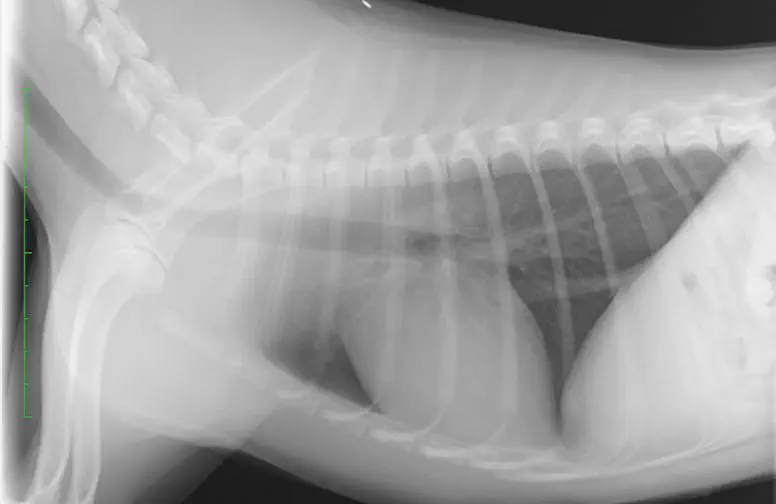

胸部レントゲン検査

肺野の異常の有無、気管および気管支の評価、胸郭や横隔膜の評価などを行います。

正常な犬の胸部